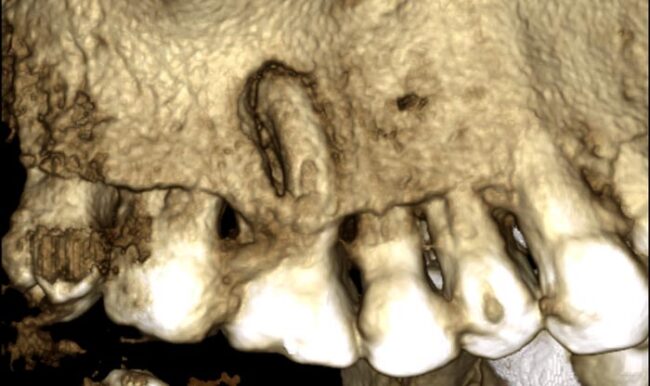

El Dr. Rubén Monge nos muestra en este caso un paciente con absceso apical severo en 1.6 con un tratamiento de conducto realizado previamente. En el retratamiento utiliza RetreatAll® para eliminar la gutapercha y BlueShaper® para la instrumentación.